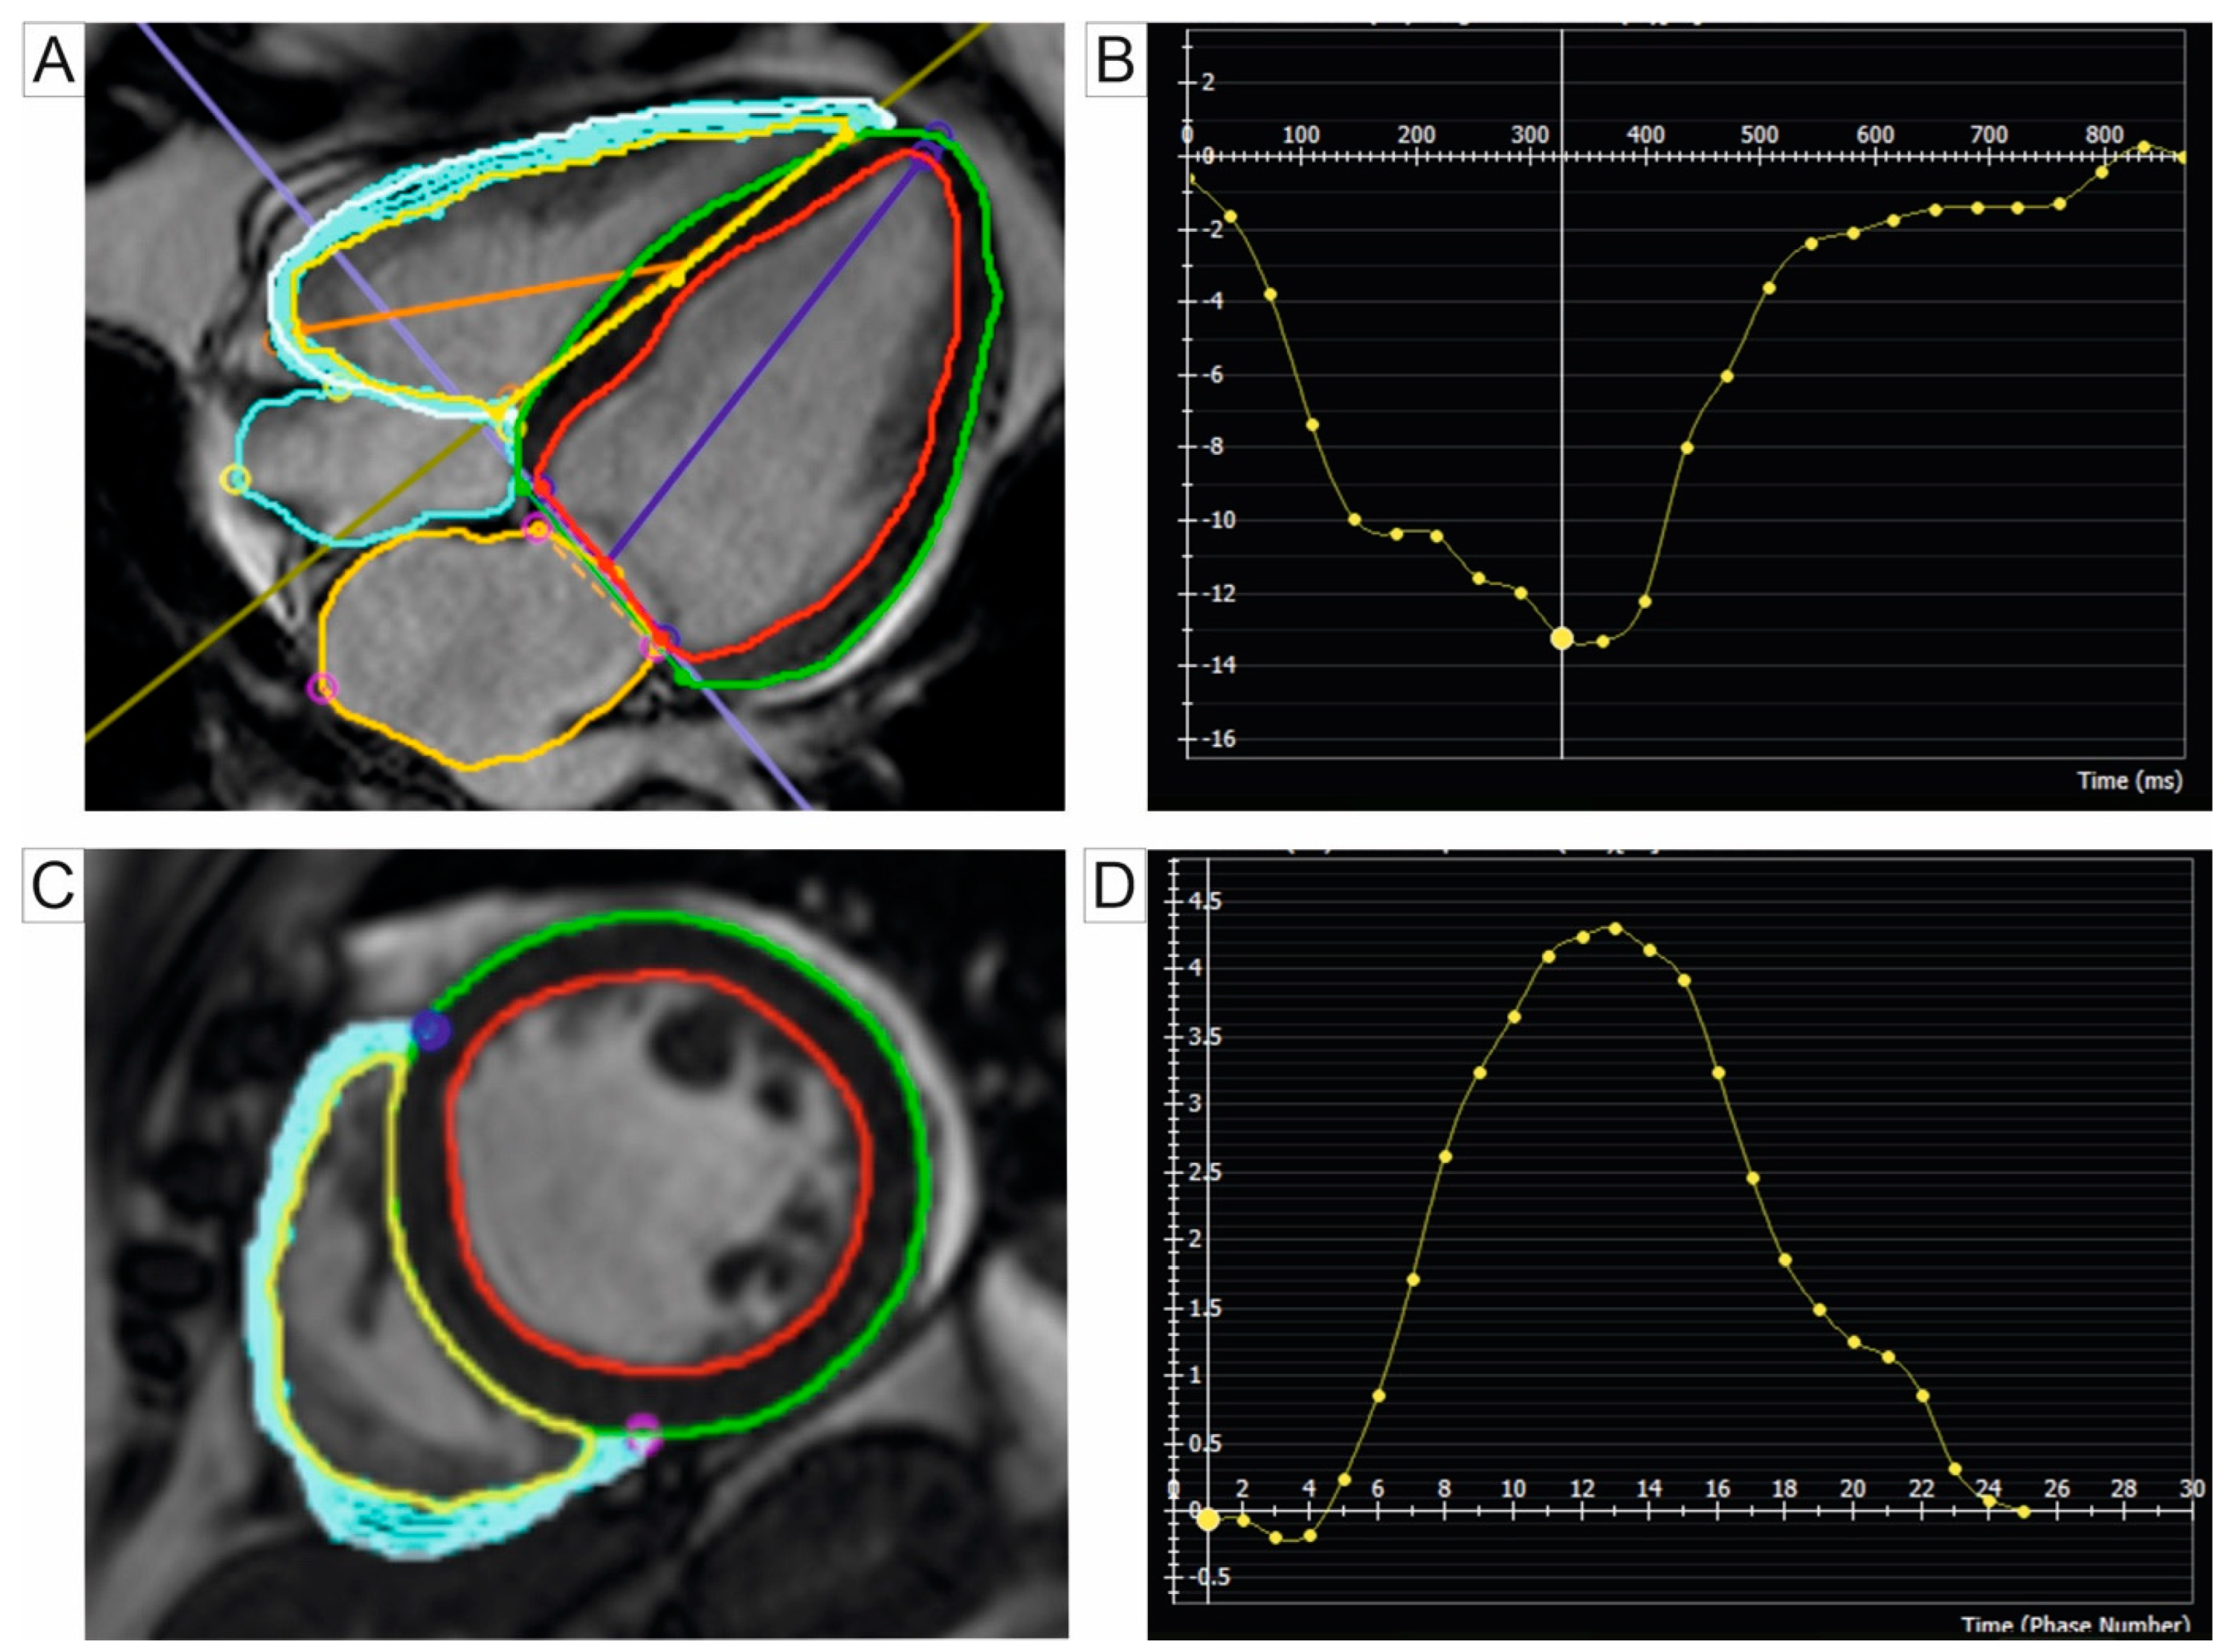

Additional echocardiographic parameters have been proposed to assess the severity of PH, many of which have important prognostic value. These include measurements of RV dimensions at the basal and mid-ventricular levels and along the longitudinal axis, as well as semi-quantitative markers of RV function such as fractional area change (FAC), tricuspid annular plane systolic excursion (TAPSE), and systolic longitudinal contraction velocity (s’) assessed via pulsed tissue Doppler [12,21]. The myocardial performance index (Tei index) is another parameter for RV systolic function, derived either from using pulsed wave Doppler at the tricuspid and pulmonary valves or from tissue Doppler imaging at the lateral tricuspid annulus [13]. Two-dimensional echocardiographic parameters used for PH evaluation are represented in Figure 1.

Figure 1. Transthoracic Echocardiography 2D views: (A) apical 4-chamber view illustrating severe tricuspid regurgitation assessed through Doppler echocardiography. (B) Subcostal view utilized for the management of the inferior vena cava and evaluation of its respirophasic collapsibility, aiding in the assessment of right atrial and PA pressures. (C) Apical 4-chamber view at end-diastole in a patient with RV dilation, determined by measuring basal, medial, and longitudinal diameters. (D) Apical 4-chamber view with M-mode for estimating lateral tricuspid annulus excursion towards the apex during systole, used as a marker of RV systolic function. (E) Pulsed-wave Doppler echocardiography for measuring the RVMPI. (F) Speckle-tracking echocardiography at the level of the RV free wall for assessing global RV deformation in a patient with PH. Abbreviations: 2D, two-dimensional; PA, pulmonary artery; RV, right ventricle; RVMPI, right ventricle myocardial performance index; PH, pulmonary hypertension; RA, right atrium; LA, left atrium; LV, left ventricle.